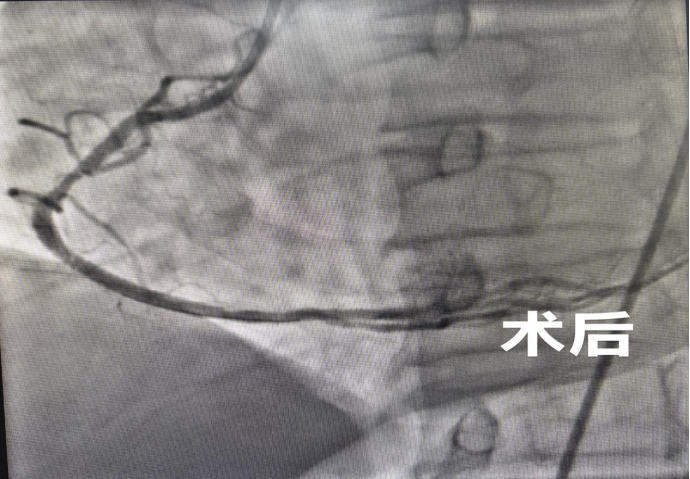

心跳虽已恢复,但患者病情仍不稳定。医院迅速启动急性心梗绿色通道,患者被第一时间送入介入导管室。心血管内科手术团队立即开展急诊冠脉造影+右冠状动脉PCI手术,精准定位堵塞血管,迅速开通血管,恢复心肌供血,从根本上解除致命威胁。手术团队配合默契、操作精准流畅,顺利完成手术。